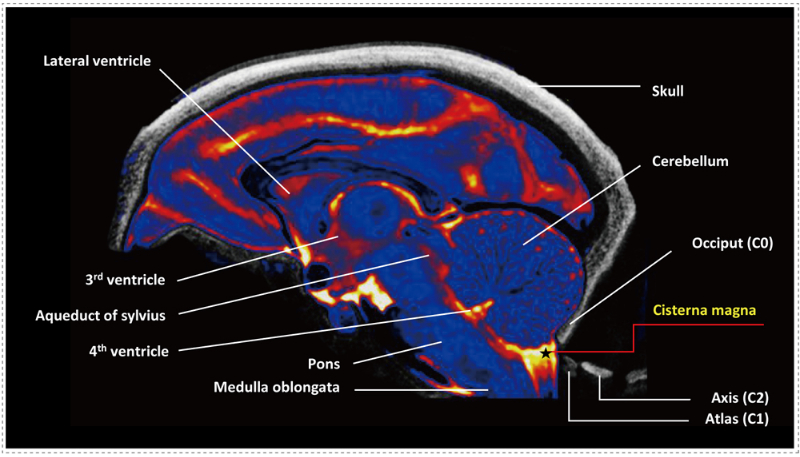

СÄÔÑÓËè³Ø³£±»ÓÃÓÚÊÕÂÞÄÔ¼¹ÒººÍÖÐÊà¸øÒ©µÈÖÎÁÆ¡£¡£¡£¡£¡£¡£¶ø½üÄêÀ´Ð¡ÄÔÑÓËè³ØÄÚ×¢ÉäÒѱ»¿ª·¢ÓÃÓÚÔöÇ¿ÖÐÊàÉñ¾ÏµÍ³Ò©ÎïÔËËÍ¡£¡£¡£¡£¡£¡£Ëæ×źËËáÀàÒ©ÎïµÄ¿ª·¢Í»·ÉÃͽø£¬£¬£¬¶à¿îÒ©ÎïÂ½Ðø»ñÅúÉÏÊС£¡£¡£¡£¡£¡£¹ÑºËÜÕËá¼°AAVÐÂÒ©Ñз¢ÁÙ´²Ç°ÌåÄÚÒ©ÀíÃæÁÙÁ½´óÌôÕ½£¬£¬£¬ÔõÑùÓÐÓõؽ«ÕâÀàзÖ×ÓµÝË͵½°ÐÆ÷¹Ù×éÖ¯£¬£¬£¬ÔõÑù½â¾öÇå¾²ÐÔÎÊÌâ¡£¡£¡£¡£¡£¡£¶øÐ¡ÄÔÑÓËè³ØÄÚICM×¢Éä¾Í¿ÉÒÔÓÐÓõÝËͶ¨Ïò´óÄԵĹѺËÜÕËá¡£¡£¡£¡£¡£¡£

ºïÄÔÖÐСÄÔÑÓËè³Ø (CM) µÄ¶¨Î»Ê¾Òâͼ[1]